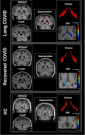

Long COVID may be triggering Alzheimer’s-like changes in the brain: new study

New York Post | Feb 10, 2026

Queensland researchers find COVID alters brain tissue

Dec 15, 2025

Scientists from Griffith University in Queensland, Austalia, have found evidence that COVID-19 can cause significant long-term brain alterations even long after the infection. They compared MRI brain scans of infected individuals with those who hadn't bee...